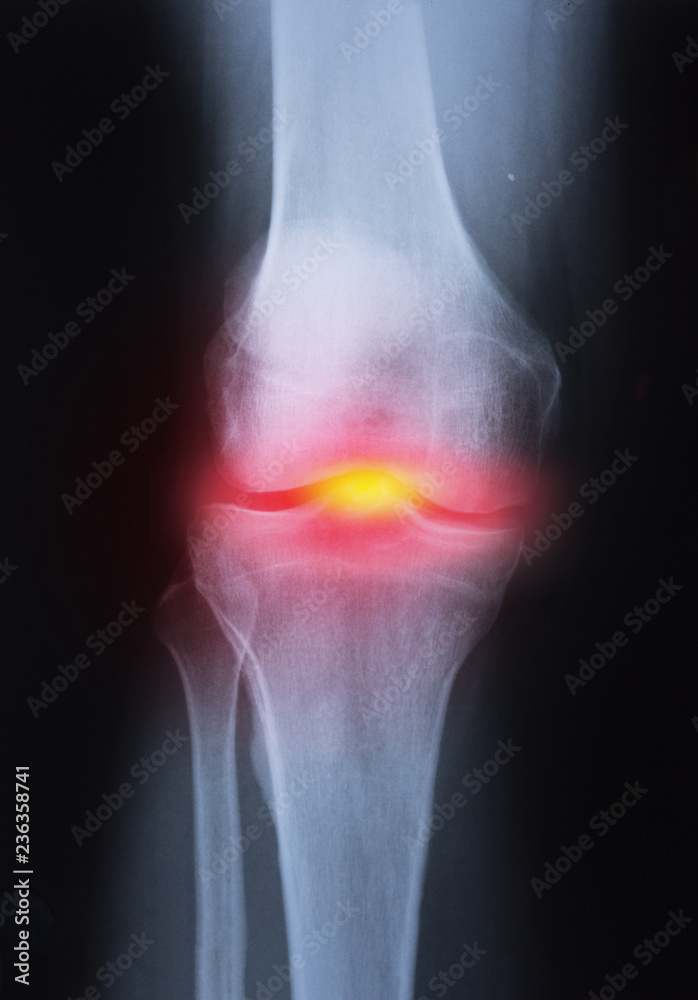

From stock.adobe.com

Medical xray knee joint image with arthritis ( Gout , Rheumatoid arthritis , Septic arthritis Septic Arthritis In Knee Joint The infection will spread to the joints and cause inflammation. Bacteria generally cause it, but sometimes, it can develop after exposure to a virus or fungus. You can make a full recovery with. Septic arthritis is also known as infectious arthritis, and is usually caused by bacteria. It should be treated as soon as possible. However, polyarticular septic arthritis involving. Septic Arthritis In Knee Joint.